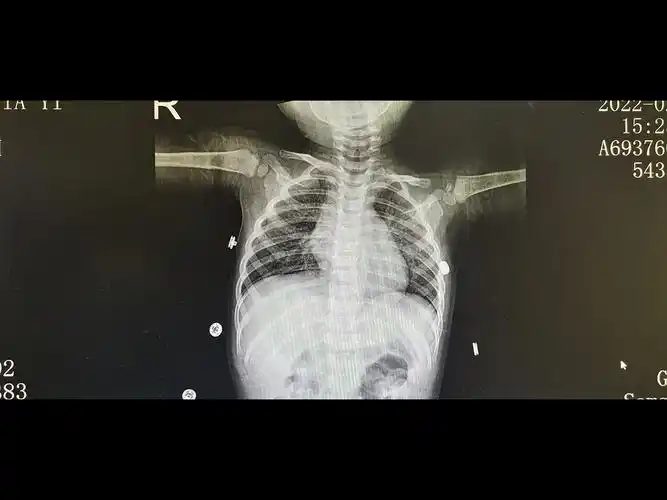

新生儿肺纹理粗不一定是肺炎,有可能是:新生儿湿肺

儿童肺炎时胸片怎么看呢